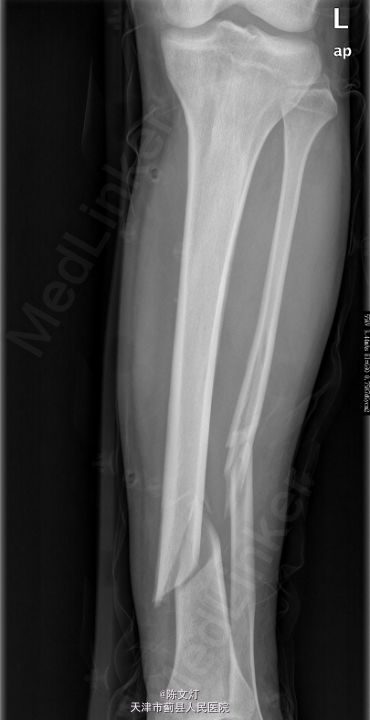

患者,男,36岁,因“车祸致左小腿疼痛伴活动受限1天”入院。

查体:左小腿活动受限,局部疼痛,皮肤感觉无殊,皮肤无破溃,趾端活动无殊,可及足背动脉搏动。其余肢体无殊,病理征未引出。辅助检查:2015-05-06 我院行CR检查提示:左胫腓骨骨折。